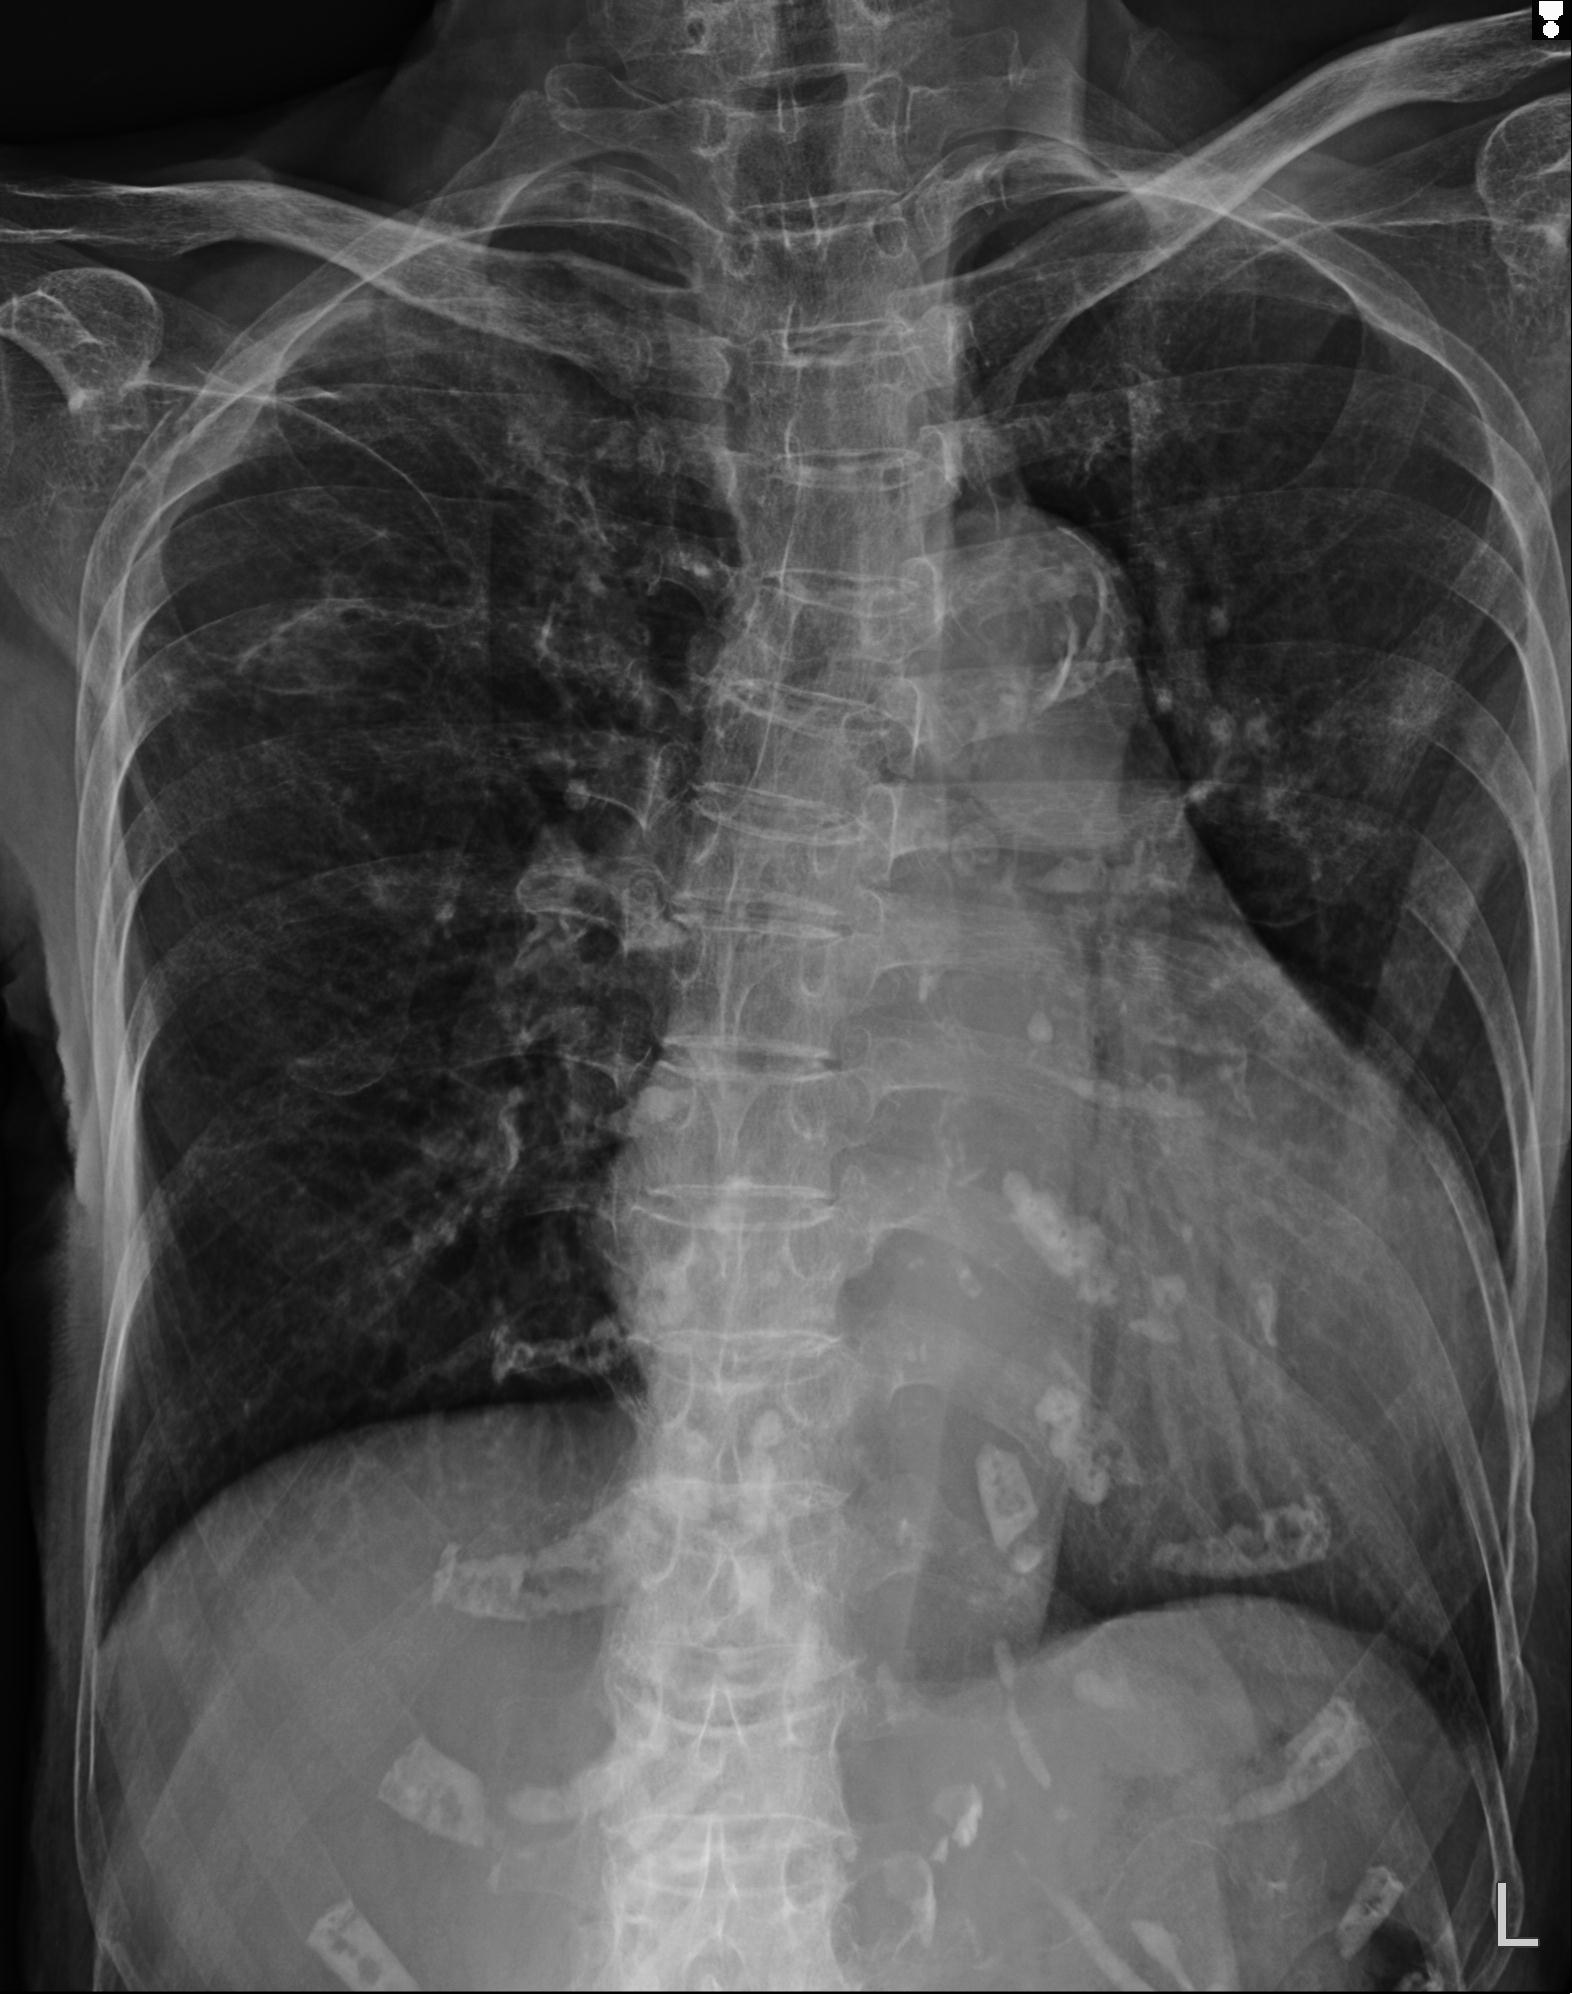

110211 1/6 1/8 左前腕 4R 15歳男性 橈骨骨幹部骨折